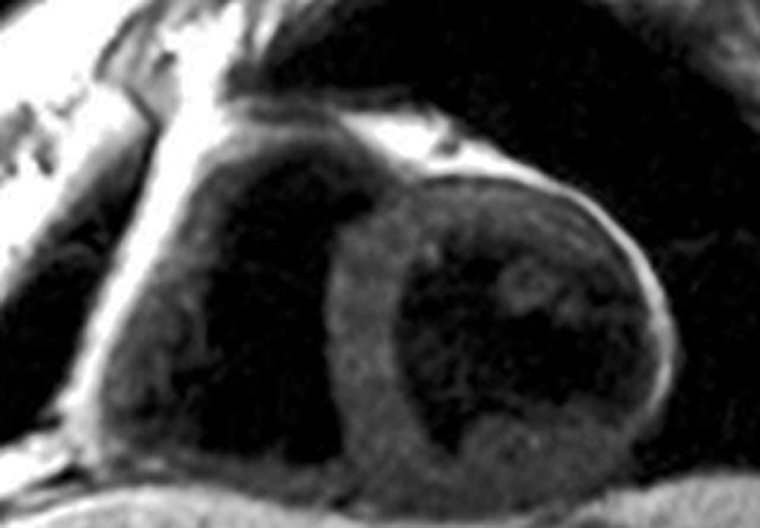

Manganese also has an affinity for the myocardium and can act as biomarker in heart disease. Manganese ions compete with calcium for entry into cardiac cells. There the ions bind to macromolecules and influence the relaxation of cell and tis­sue water. Heart diseases gradually inactivate calcium transport mechanisms due to lower metabolic activity. Thus, manganese uptake is reduced accordingly; man­ga­nese-induced changes of tissue relaxation reflect tissue calcium homeostasis and thus myocardial viability (Figures 13-17 and 13-18) [⇒ Skjold 2004, ⇒ Skjold 2007] and allows the assessment of stunned and viable myocardium [⇒ Spath 2021, ⇒ Singh 2023].

Figura 13-17:

Mn-DPDP: A short axis single shot IR Turbo-FLASH image of a heart before contrast agent application (top), and another image of the same heart with the same parameter settings one hour after the end of the contrast agent infusion (bottom).

To the right of each image sectoral divisions of the left ventricle are shown, depicting R1 color maps of the respective slice. The left ventricle shows a marked change in contrast (modified from Skjold 2004).